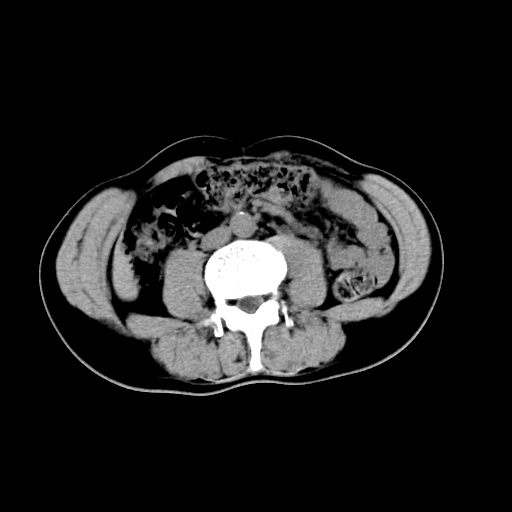

男,47岁,左输尿管结石碎石治疗后10余日。彩超示:左输尿管下段狭窄、输尿管积水。请各位讨论一下左输尿管下段结石还是静脉石?

象是第二狭窄处结石伴以上输尿管、肾盂轻度积水。

输尿管结石伴以上输尿管、肾盂轻度积水。

两侧髂总动脉壁斑状及点状钙化.左侧输尿管行经与左髂总动脉相交后见高密度影,且下段输尿管管腔未见扩张,应该要考虑结石伴以上输尿管及肾盂积水.但右侧结节状高密度影,也应该是结石吧!那以上输尿管未见扩张呢!因此静脉结石可能性也较大.请问楼主碎石前左侧输尿管结石位置.

虽左侧有轻度肾盂积水但不支持结石。1结石边周应该有软组织包绕呈晕征。2钙化点前面见输尿管影也不支持是结石。3彩超没提结石。建议超生复查。

输尿管先位于腹部,后进入盆腔,最后斜穿膀胱壁开口于膀胱,因此,临床上常将输尿管分为腹段、盆段和壁内段。第1个狭窄:在肾盂与输尿管移行处。第2个狭窄:在跨过髂血管处。第3个狭窄:在穿过膀胱壁处。这些狭窄是结石容易滞留的部位。

左侧输尿管有轻度扩张伴有肾盂积水,输尿管下段周围的高密度影不象在输尿管内。

同意,不支持结石。(因显示该高密度影前见扩张输尿管影,另外两侧对称显示)。

左侧高密度影在左侧输尿管的内侧方,所以不考虑输尿管结石.

我认为不是结石的可能性大,因为他的位置和血管钙化的位置邻近